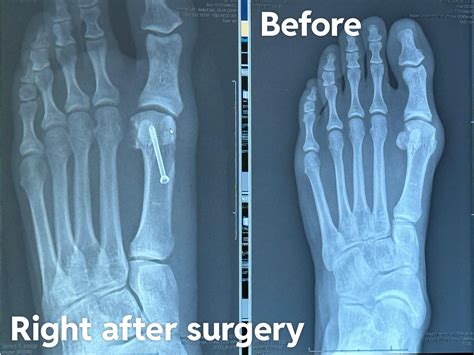

Before and After Bunion Surgery Photos | The Bunion Cure